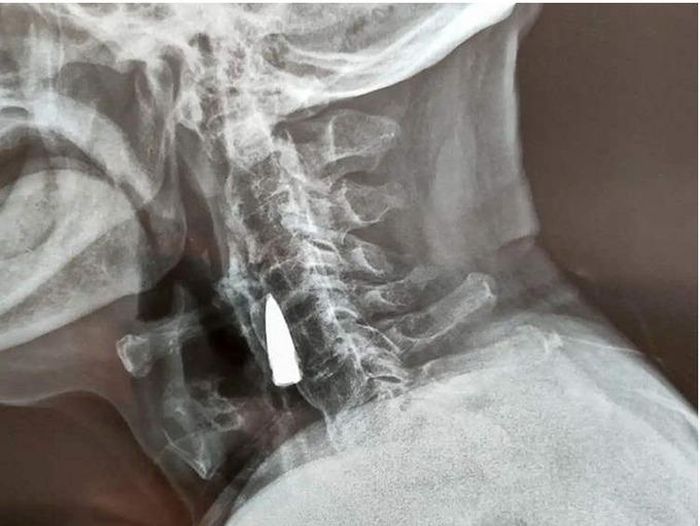

Kết quả chụp X-quang cho thấy một dị vật ở cổ ông Zhao He, được xác định là một viên đạn cũ.

Viên đạn găm trong cổ người cựu chiến binh gần 80 năm.

Ông Zhao He linh cảm có thể viên đạn đã găm vào cổ ông từ năm 1944 lần ông bị trúng đạn khi băng qua sông. Viên đạn được cho là đã xuyên qua bên trái mũi, xuyên qua hàm trên và làm gãy răng của ông trước khi găm vào cổ.